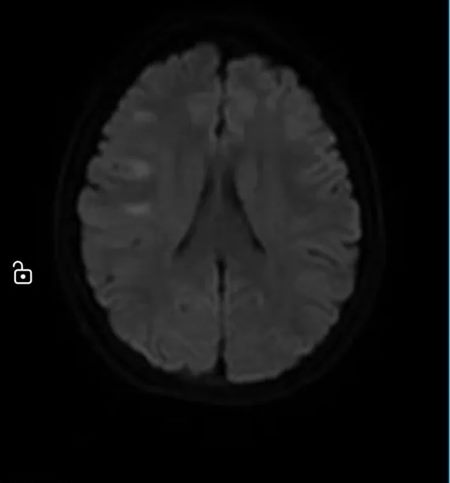

清晨,急诊科送来一名12岁的女孩。突发偏瘫、不能说话——确诊为“急性脑梗死”。

640 (3)_副本

640 (4)_副本

她未满18岁,不符合常规溶栓指征。

只有另辟蹊径才能点亮生命之光!

绿色通道立即开通,多学科团队火速集结。

神经内科评估、神经外科接力、影像瞬间出片……

最终决定:脑血管造影 + 经皮颅内动脉取栓术。

手术台上,团队从她堵塞的颈内动脉中,取出一条近10厘米长的血栓。

640 (5)_副本

血流恢复的那一刻,手术室里所有人都松了一口气。